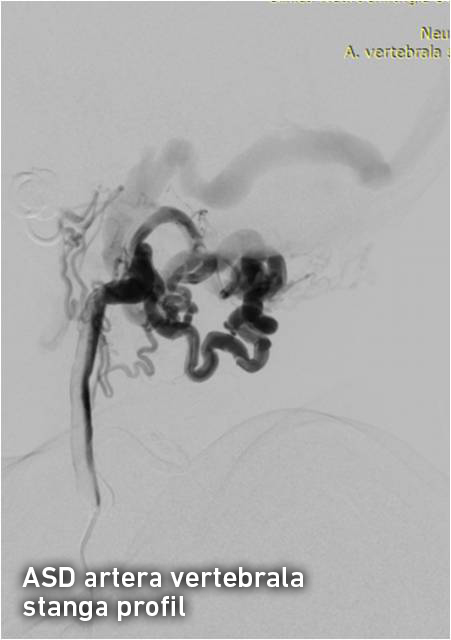

Pentru precizarea diagnosticului a fost nevoie de o investigație invazivă și anume angiografia cu substracție digitală a vaselor capului și gâtului, ce reprezintă „standartul de aur “ în patologia neurovasculară. Angiografia clasică diagnostică a confirmat existența unei fistulei arterio-venoase posttraumatice cervicale pe stânga și ocluzia venei jugulare stângi. Fistula arterio-venoasă posttraumatică reprezintă comunicarea anormală dintre sistemele venos și arterial apărută după leziunea peretelui vascular. În cazul dat sângele arterial din artera vertebrală stângă și trunchiul tireo-cervical stâng pătrundea sub presiune înaltă în porțiunea incipientă a venei jugulare stângi, apoi retrograd în sinusul sigmoid stâng, sinusurile transverse, sinusul sigmoid drept și se drena extracranian prin vena jugulară dreaptă. Arterializarea sângelui din sinusurile venoase ale durei mater are ca consecință creșterea presiunii venoase intracraniene, apariția stazei venoase și dilatarea venelor cerebrale superficiale și profunde. Ca rezultat, bolnavii cu fistule arterio-venoase a vaselor precerebrale și cerebrale suferă de dureri de cap și de ochi, dereglări cognitive, afectarea nervilor cranieni (conflict neuro-vascular cu n. trigemen și n. facial) și acufene. Hipertensiunea venoasă intracraniană poate cauza accidente vasculare hemoragice, ce reprezintă una din cauzele principale de morbiditate şi mortalitate.

Tratamentul endovascular a fost realizat grație colaborării multidisciplinare între neurochirurgul-intervenționist Alexandru Șumleanschi, cardiologul-intervenționist Eugen Calenici și neuro-anestezisteziolog Iana Cotorcea. Embolizarea a avut loc în 2 etape sub anestezie generală : pe 15.07.2016 a fost ocluzată artera cervicală ascendentă stângă (trunchiul tireo-cervical) cu Onyx și pe 02.09.2016 a fost realizată ocluzia arterei vertebrale stângi (segmentul V2-V3). Toate obiectivele propuse înainte de operație au fost realizate cu succes. Starea pacientului s-a ameliorat după embolizare: au dispărut acufenele, au diminuat durerile nevralgice, ceea ce a permis diminuarea tratamentului neurotrop. Spre deosebire de chirurgia clasică, pacientul a necesitat timp redus de spitalizare și recuperarea după embolizare a fost rapidă.